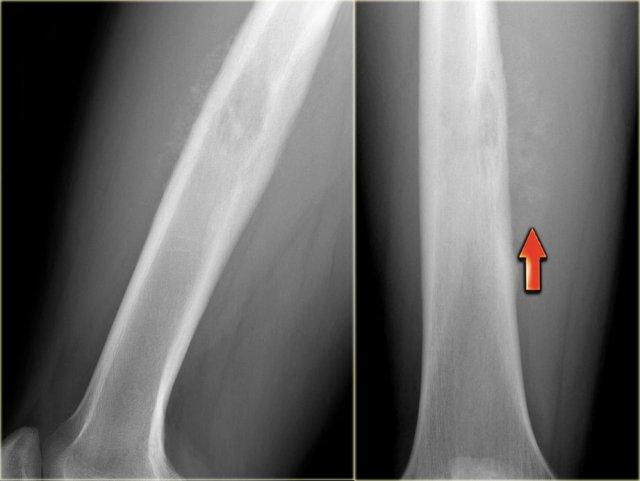

Ewing’s sarcoma in diaphysis of the femur. Notice ill-defined zone of transition (blue arrow) and aggressive type of periosteal reaction (red arrows)

Bên trái là hình ảnh bệnh nhân có u xương Ewing ở xương đùi.

Lưu ý vùng tiêu xương không rõ ranh giới.

Có phản ứng màng xương xâm lấn.

Bên trái là một tổn thương tiêu xương không rõ ranh giới ở xương đùi của bệnh nhân trẻ tuổi.

Có hình thái phá hủy thấm nhiễm với sự phá hủy vỏ xương không đều.

Có phản ứng màng xương dạng xâm lấn (mũi tên).

Hình ảnh này còn được gọi là hình ảnh tia mặt trời.